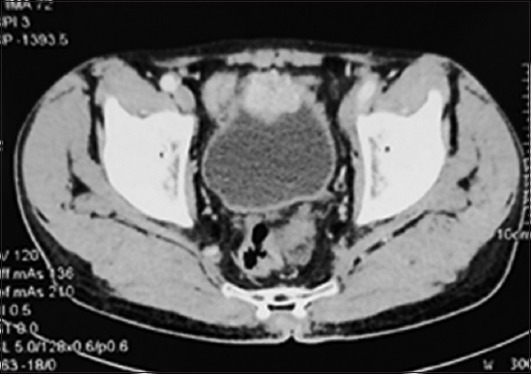

Case presentation: Presented here are three cases of incidental urinary bladder paraganglioma, all having hematuria as the primary symptom. During transurethral resection of bladder tumor, blood pressure fluctuated intensely with profuse bleeding, leading to the abandonment of the procedure. The patients were later diagnosed as having paraganglioma, and then, they were subjected to systemic evaluation and definitive treatment.